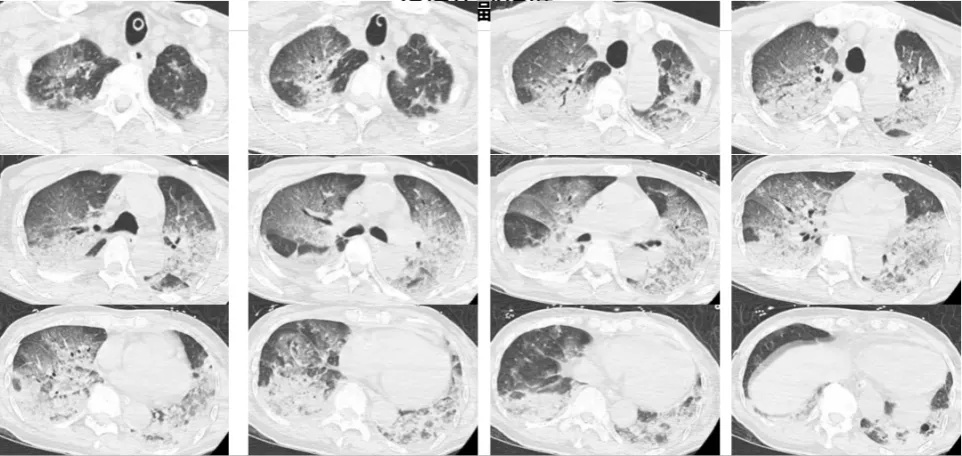

接诊后,医生们一度怀疑韩大爷有肺栓塞或者脑梗,韩大爷意识不清,血压下降、心率也降到30次/分,氧饱和度只有80%到90%之间,急查血气显示pH仅有7.094,二氧化碳分压高达77.4mmHg,有明显的Ⅱ型呼衰和呼吸性酸中毒,于是立即启动抢救程序。韩大爷插管后被立即送到CT室进行了头颅和胸部CT和肺血管CTA检查。

结果一出来,大家吓了一跳,两肺全白了!

医生检查后排除了脑中风和肺栓塞的可能性,经过及时抢救,韩爷爷各项检查指标也有了明显改善,但问题是到底是什么病导致这样的白肺呢?

医院供图